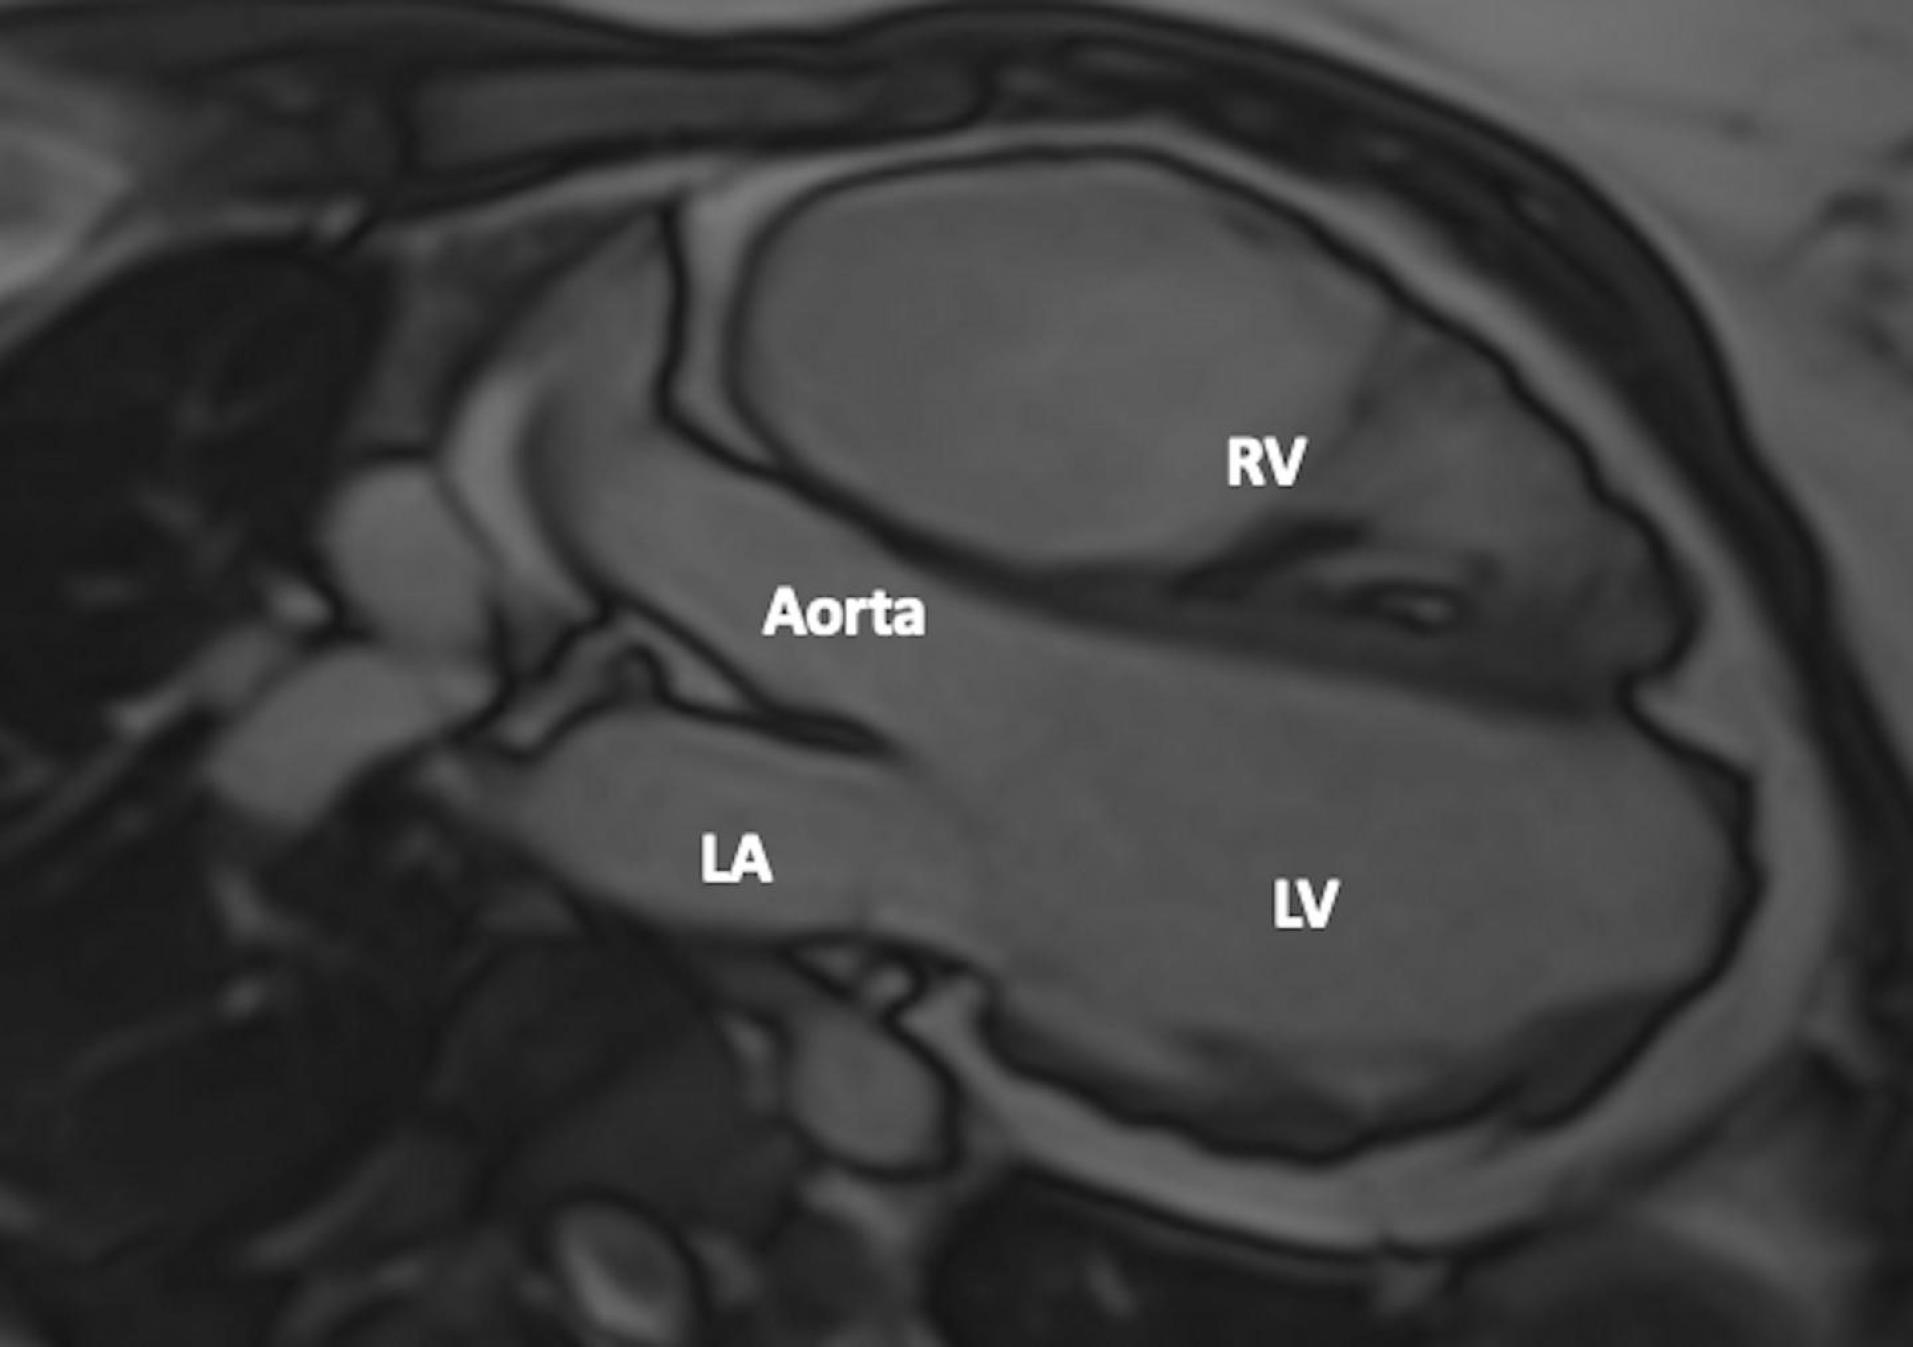

Figure 3.

Wall Irregularity in Both Right and Left Ventricles. CMR 3-chamber view shows wall irregularity in both the right and left ventricles. FIGUR LEGEND: CMR: Cardiac Magnetic Resonance, LA: Left Atrium, RV: Right Ventricle, LV: Left Ventricle.

A 24-year-old female patient was admitted to our tertiary center with chest pain. She had no family history of cardiac disease or sudden cardiac death. Her electrocardiogram (ECG) was sinus rhythm and T wave negativity was detected in leads V1-5. (Figure 1) TTE showed a slight decrease in LV ejection fraction as 45%, prominently dilated right heart chambers, decreased RV functions (TAPSE: 11, tricuspid annular peak systolic velocity: 7.7), severe tricuspid regurgitation (Supplementary file 1, Video 1). Additionally, an image of 13.6 x 9.3 mm, hyperechoic, consistent with thrombus was observed in the lateral wall of the RV (Figure 2). No thromboembolism was reported in the pulmonary CTA. The patient underwent cardiac magnetic resonance imaging (CMR) for morphological and functional assessment of the heart. The CMR images showed enlarged RV and right atrium, severe hypokinesia of the RV, dyskinesia in the free wall of RV and paradoxical movement in interventricular septum, and wall irregularity in both ventricles (Figure 3). In the cardiac MRI, The LV ejection fraction was 49%, the LV end-systolic volume was 143 mL, end-diastolic volume was 73 mL, and stroke output was 60 mL. The LV end-diastolic volume index (LVEDVI) was 74 mL/m2, the LV end-systolic volume index (LVESVI) was 42 mL/m2. The RV ejection fraction was 20%, the RV end-systolic volume was 430 mL, end-diastolic volume was 343 mL, and stroke output was 87 mL. The RV end-diastolic volume index (RVEDVI) was 221 mL/m2, the RV end-systolic volume index (RVESVI) was 176 mL/m2. The late gadolinium images depicted diffuse enhancement in the right ventricular free wall and inferior wall. The left ventricular inferior septum showed midwall enhancement. A nodular mass was noted on the lateral wall of RV in the vicinity of the tricuspid valve which did not uptake gadolinium and was compatible with thrombus (Figure 4). As a result of these findings, genetic analysis was performed with a high suspicion of arrhythmogenic cardiomyopathy. The genetic analysis revealed a homozygous nonsense mutation in the desmoglein-2 gene, proven to be pathogenic in databases, and the diagnosis of arrhythmogenic cardiomyopathy was definitively confirmed with the findings from TTE, ECG, CMR, and genetic tests, which are part of the aforementioned Padua criteria.